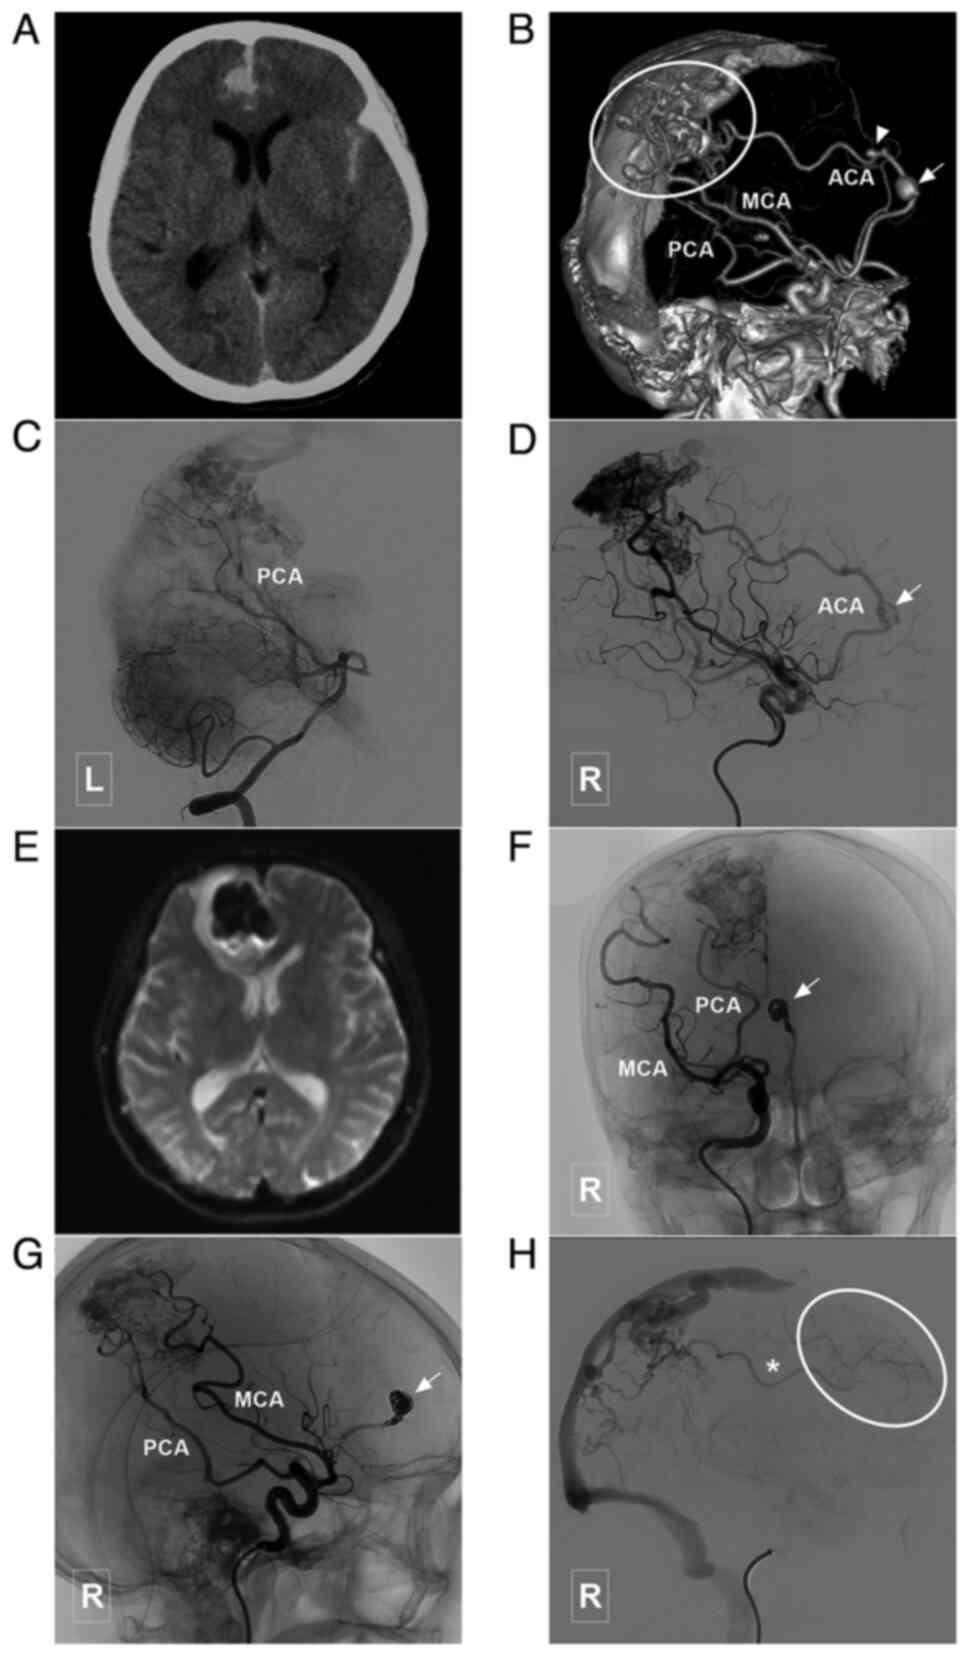

Figure 7

Typical case of a type III BAVM with multiple flow-related aneurysms in the ACA trunk. (A) Head CT scam illustrating a subarachnoid hemorrhage in the interhemispheric fissure. (B) Head CTA illustrating a BAVM (encircled area) supplied the ACA, MCA and PCA, and which drained to the sagittal sinus. The ACA is the main feeding artery, with multiple flow-related aneurysms (arrow and arrow head). (C) Angiogram of the left vertebral artery shows that the posterior circulation is involved in the blood supply of the BAVM. (D) A stent was used to assist in coiling of the aneurysm (arrow) in the ACA. (E) MRI at 3 days post-treatment reveals a new hemorrhage in the interhemispheric fissure, which is considered to be caused by re-rupture of the aneurysm. (F and G) Parent artery occlusion is performed to occlude the aneurysm and the parent artery (arrow). (H) Angiogram of the right internal carotid artery in venous phase illustrating retrograde blood supply from the BAVM to the frontal lobe (encircled area) through the ACA (asterisk). ACA, anterior cerebral artery; BAVM, brain arteriovenous malformation; CT, computed tomography; CTA, computed tomography angiography; L, left; MCA, middle cerebral artery; MRI, magnetic resonance imaging; PCA, posterior cerebral artery; R, right.

Figure 8

Typical case of a type III BAVM with aneurysm in the lenticular artery. (A) Head CT scan illustrating an intraventricular hemorrhage. (B) Head CTA illustrating a BAVM (encircled area) near the midline. (C and E) Two-dimensional (C and E) and three-dimensional (D) angiogram illustrating a BAVM supplied by the ACA and lenticular artery of the MCA. The asterisk in panels C and D denotes the lenticular artery. The arrowhead denotes the aneurysm in the lenticular artery. Pial collateral circulation from the PCA also supplies the BAVM (asterisk in panel E). (F) Unsubtracted angiogram illustrating that the aneurysm is occluded with coils and Onyx (encircled area). (G) Post-treatment CT scan illustrating external ventricular drainage. (H) Angiogram of the right internal artery 6 months post-treatment showing no recurrence of the aneurysm. ACA, anterior cerebral artery; BAVM, brain arteriovenous malformation; CT, computed tomography; CTA, computed tomography angiography; MCA, middle cerebral artery; PCA, posterior cerebral artery; R, right.